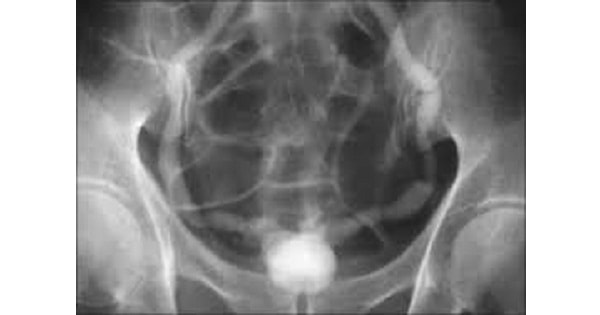

Treatment of typical condition of bladder as shown in the picture below is ?

D. a and c.